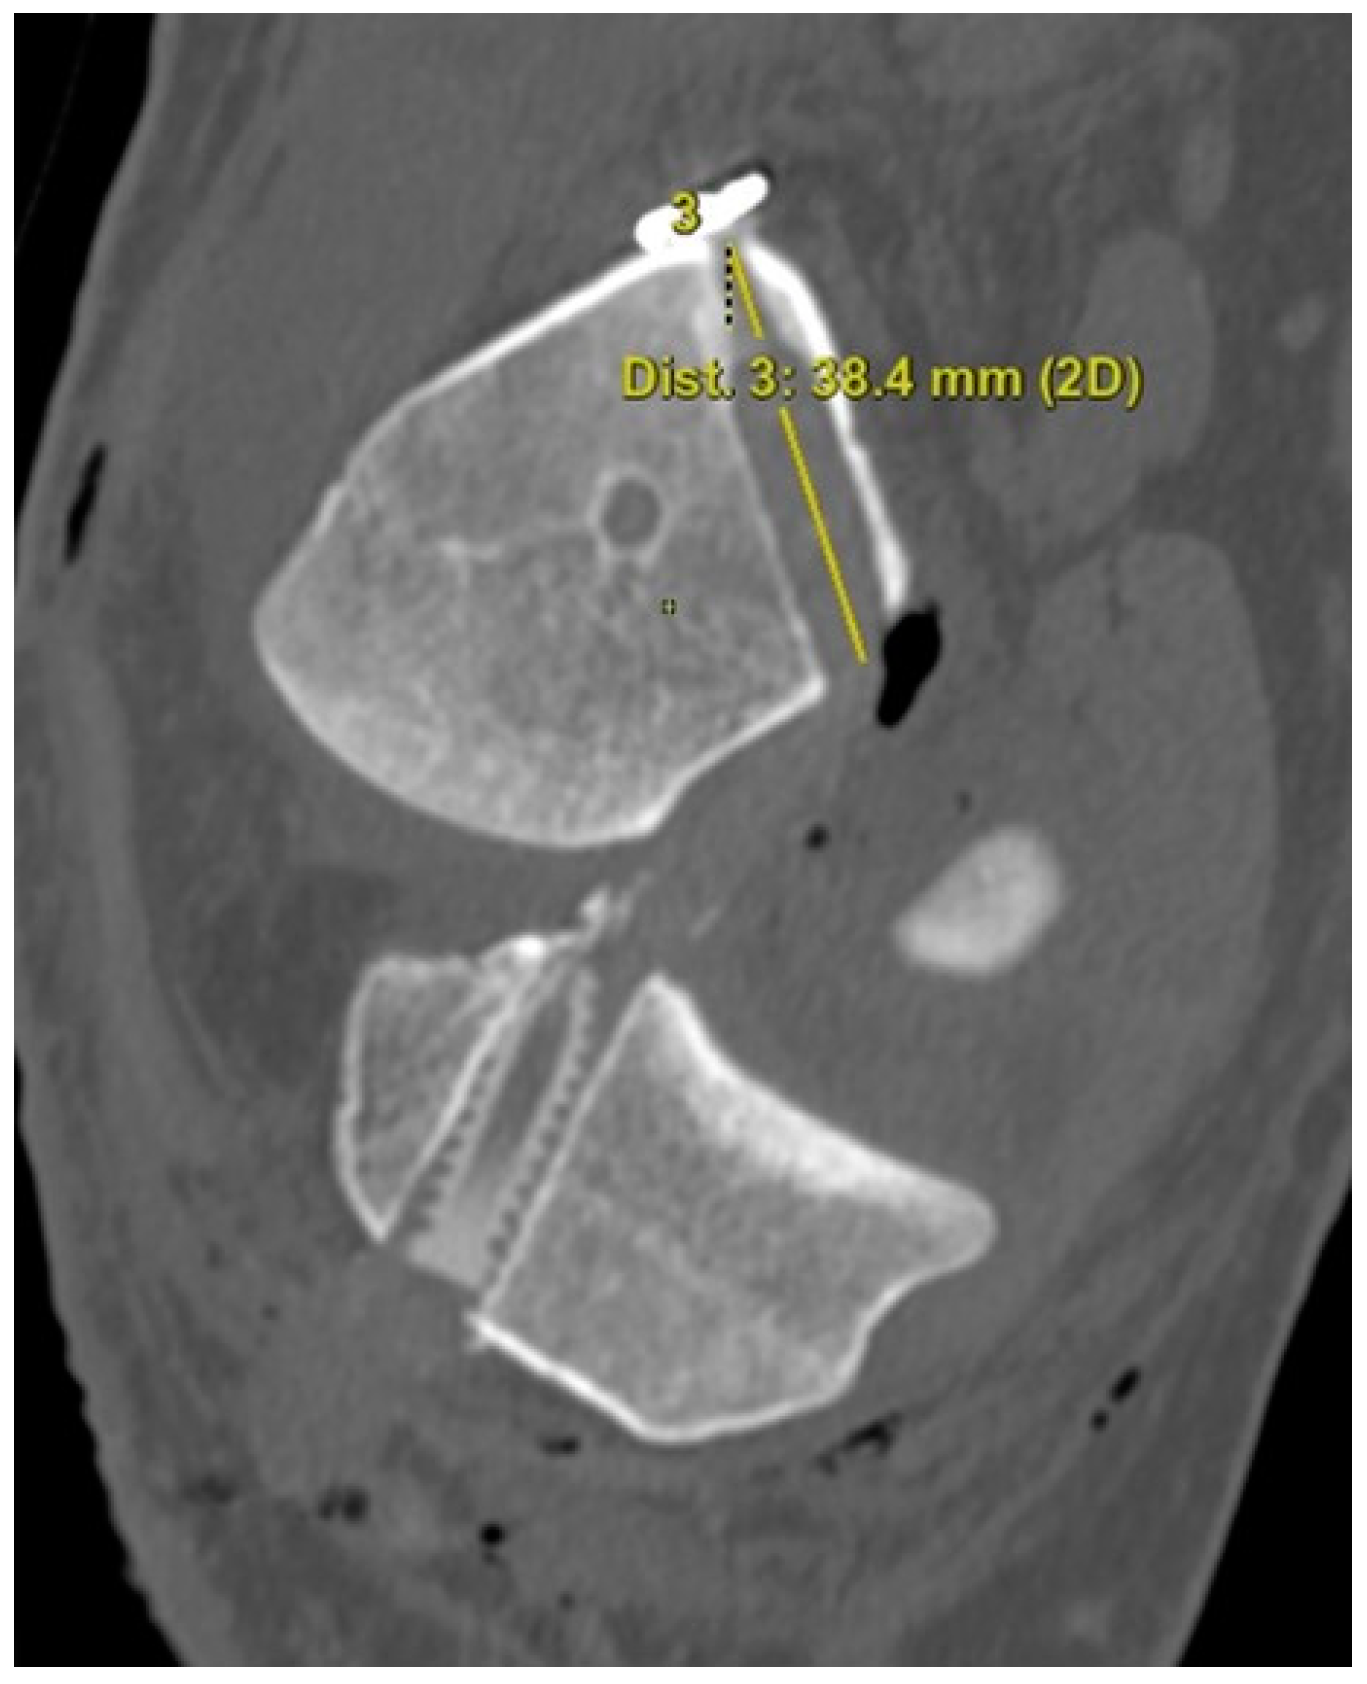

The 3D CT scans were imported into 3D software (AW Sever 3.2 PACS system, GE Healthcare; Chicago, IL, USA) for the assessments of the femoral graft bending angle and femoral tunnel length. The femoral graft bending angle was defined as the angle formed by the longitudinal axis of the femoral tunnel and the line connecting the intra-articular aperture of the tibial tunnel and the intra-articular aperture of the femoral tunnel (Figure 3). The femoral tunnel length was defined as the distance between the center of the extra-articular aperture of the femoral tunnel and the center of the intra-articular aperture of the femoral tunnel in a plane where the entire femoral tunnel could be viewed (Figure 4). Posterior wall breakage of the femoral tunnel was also checked.

Figure 4.

The femoral tunnel length is defined as the distance between the center of the extra-articular aperture of the femoral tunnel and the center of the intra-articular aperture of the femoral tunnel.